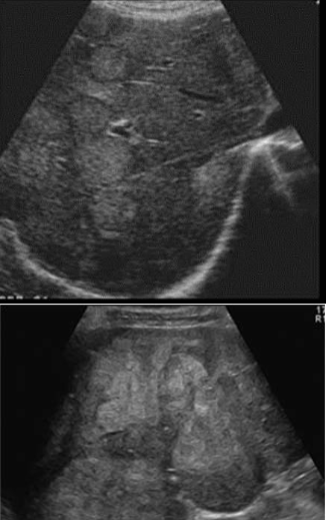

hepatoblastoma

kaposi sarcoma (KS)

metastasis